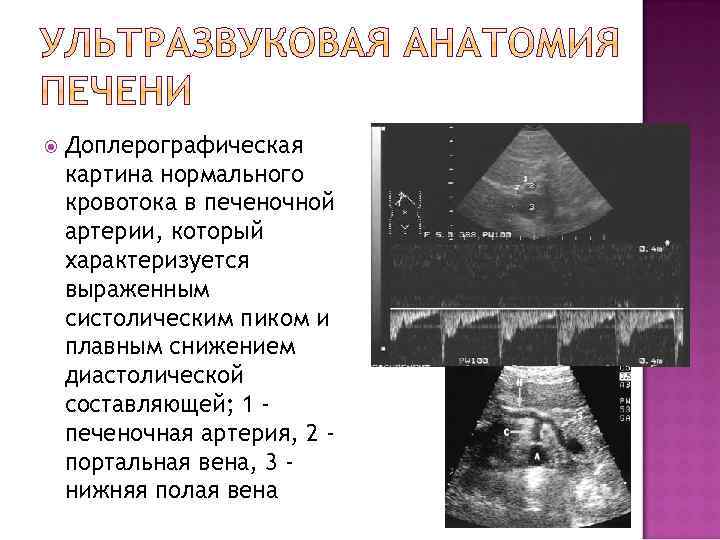

Доплерографическая картина нормального кровотока в портальной вене, который характеризуется постоянной скоростью, без систолодиастолической разницы спектра

Доплерографическая картина нормального кровотока в печеночной вене, который характеризуется пилообразным спектром без диастолической составляющей

Доплерографическая картина нормального кровотока в печеночной артерии, который характеризуется выраженным систолическим пиком и плавным снижением диастолической составляющей; 1 печеночная артерия, 2 портальная вена, 3 нижняя полая вена